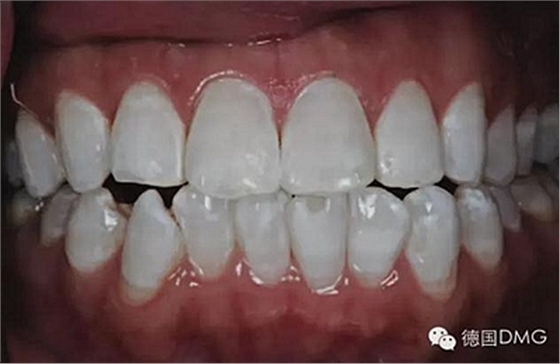

一28歲女性患者來我院修復(fù)科就診,主訴為前牙嚴(yán)重的牙齒著色和缺損十余年,要求改善牙齒的美觀。臨床檢查表明該患者有重度氟斑牙,極大的影響了前牙美學(xué)。

考慮到患者為年輕人,保守治療方法比傳統(tǒng)侵入性治療手段更為合適。術(shù)前牙周治療預(yù)防牙齦炎癥和改善牙齦健康狀態(tài),隨后聯(lián)合采用釉質(zhì)打磨、牙漂白和樹脂滲透來處理牙釉質(zhì)表面。

5、由于氟斑牙存在釉質(zhì)礦化不全等問題,家庭漂白兩周后,使用標(biāo)準(zhǔn)的樹脂滲透技術(shù) (Icon, DMG Products, Hamburg. Germany) 來預(yù)防釉質(zhì)齲。最后,徹底改變患者的前牙美學(xué),并在一年后仍保持穩(wěn)定。